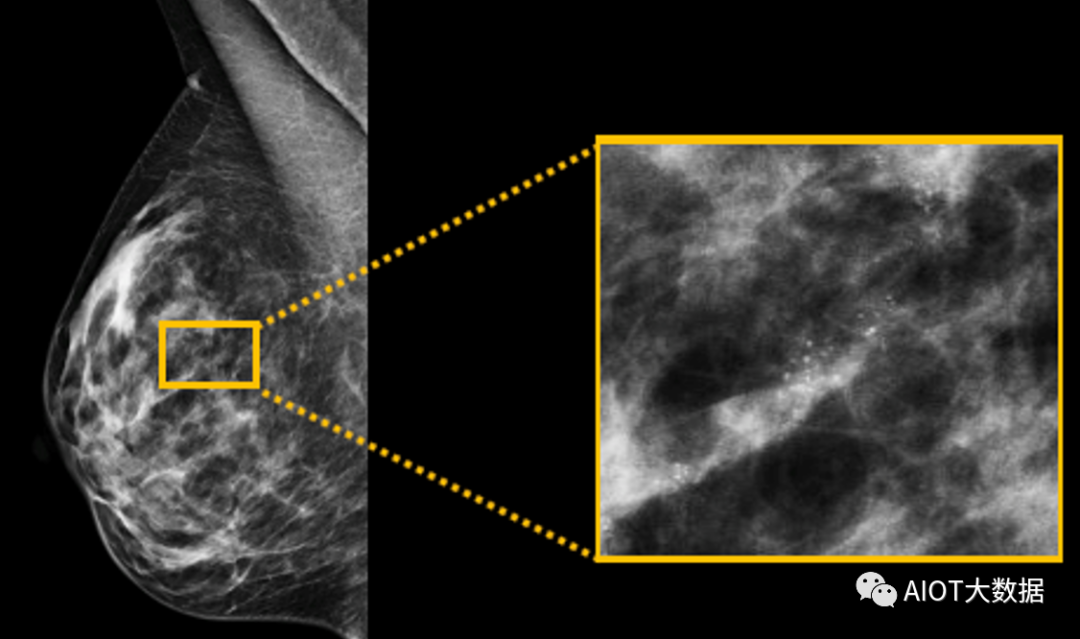

乳腺检查非晶硒技术优势明显(来自互联网)目前,在乳腺X射线成像领域,非晶硒几乎是“王者”,高端乳腺机基本均采用非晶硒平板;不过因为价格原因,也有大量主打早期筛查的高性价比乳腺机采用非晶硅平板。此外,在乳腺断层成像领域,凭借高帧速、高分辨率、高低剂量DQE等性能,CMOS平板成为乳腺TOMO/DBT的更好选择。